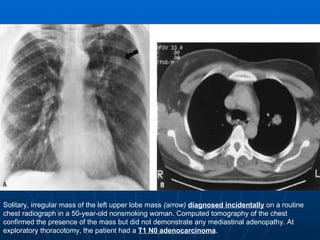

Solitary, irregular mass of the left upper lobe mass  (arrow)   diagnosed incidentally  on a routine chest radiograph in a 50-year-old nonsmoking woman. Computed tomography of the chest confirmed the presence of the mass but did not demonstrate any mediastinal adenopathy. At exploratory thoracotomy, the patient had a  T1 N0 adenocarcinoma .

Solitary, irregular massof the left upper lobe mass (arrow) diagnosed incidentally on a routine chest radiograph in a 50-year-old nonsmoking woman. Computed tomography of the chest confirmed the presence of the mass but did not demonstrate any mediastinal adenopathy. At exploratory thoracotomy, the patient had a T1 N0 adenocarcinoma .